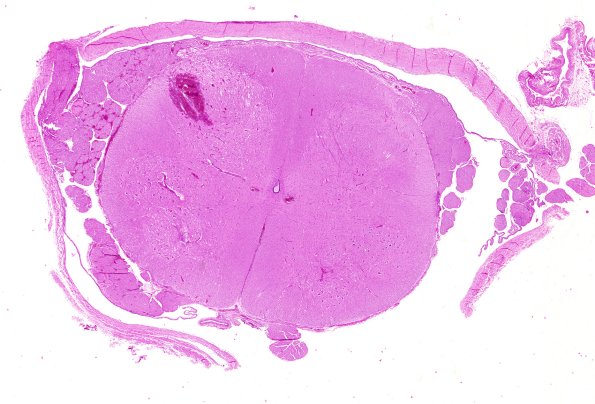

2B1,2 In this case the spinal cord in the lumbosacral region (lumbar DRG was taken) shows a focal hemorrhage at the dorsal root entry zone. (H&E)